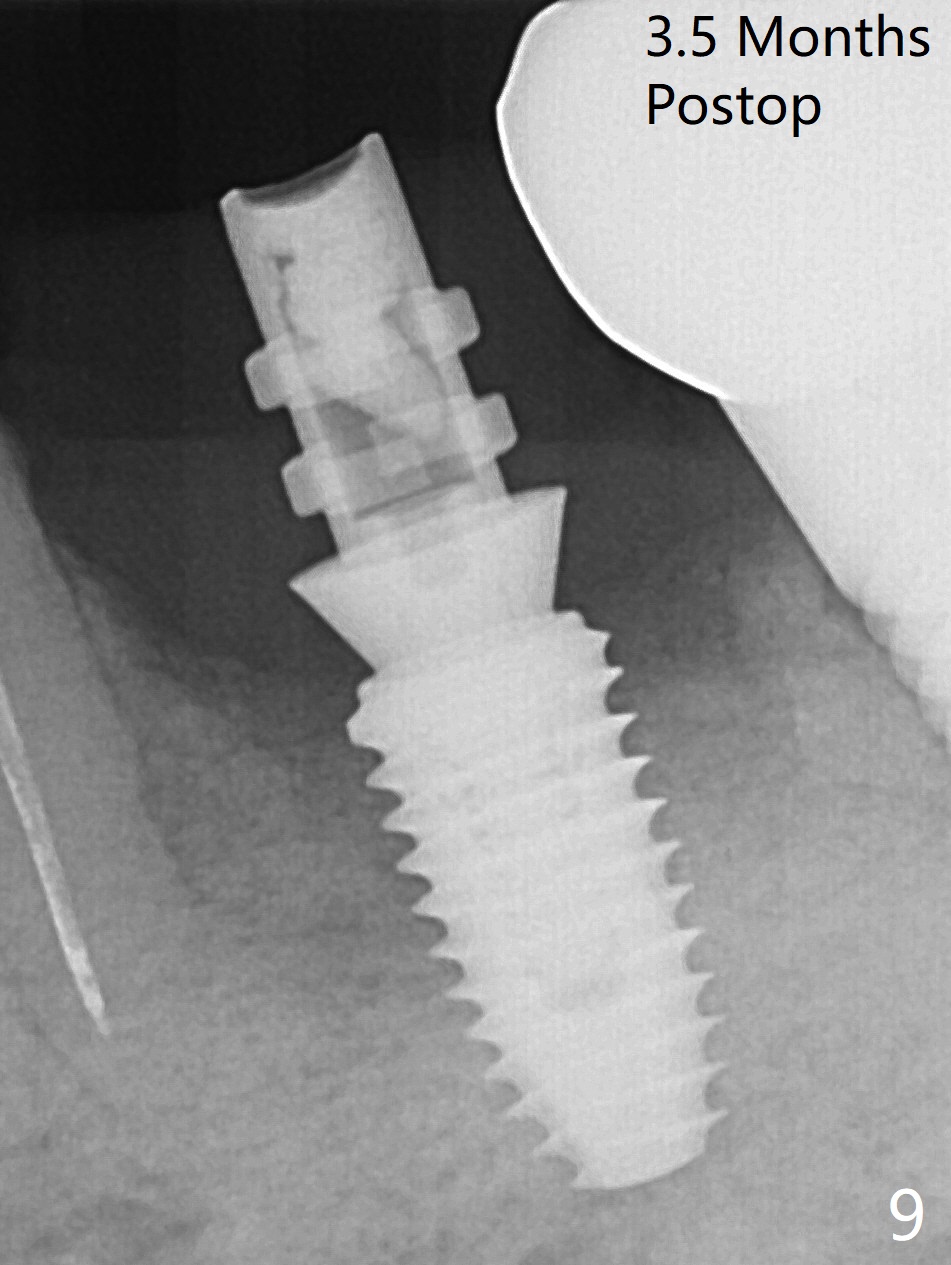

Extraction of the residual roots at #19 (Fig.1) is difficult, partially due to the hard one. The latter contributes to primary stability of 5x10 mm IS implant placed in the septum (Fig.2 (*),3). After change of cementation abutment (5.2x4.5(2) mm (short for provisional)) to hexed temporary abutment (5.2x8(2) mm), Collagen plug and Vera Graft are placed in the remaining mesial and distal socket (Fig.4 *). The last PA is taken when the temporary abutment (Fig.6 (<: hexed portion)) and provisional (P) are removed for modification. Before the abutment/provisional complex returns, a 2nd round of graft is placed (Fig.5 *). After the complex is seated, a 3rd round of graft is placed buccally (Fig.7). The temporary abutment is retightened 2 months postop (Fig.8). The implant appears to be osteointegrated 3.5 months postop (Fig.9). The gingiva looks healthy with (Fig.10) and without the provisional (Fig.11,12). It appears that there is no or minimal buccal plate loss. After insertion of a 5.7 x3 mm 15 degree (B-type) angled abutment (Fig.13) and height adjustment, impression is taken. The provisional is reseated after impression. The mesial bony defect seems to have been repaired nearly 8 months postop, 3 months post cementation (Fig.14 *). The bone density increases mesially 11 months post cementation (Fig.15).